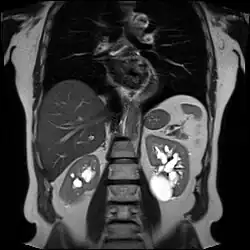

-

Renal ultrasonography of a simple renal cyst with posterior enhancement. -

Advanced polycystic kidney disease with multiple cysts.[13] -

Renal cyst as seen on abdominal ultrasound -

A very small (8 mm) simple renal cyst. -

Bosniak II cyst at the lower pole of right kidney with septations within.